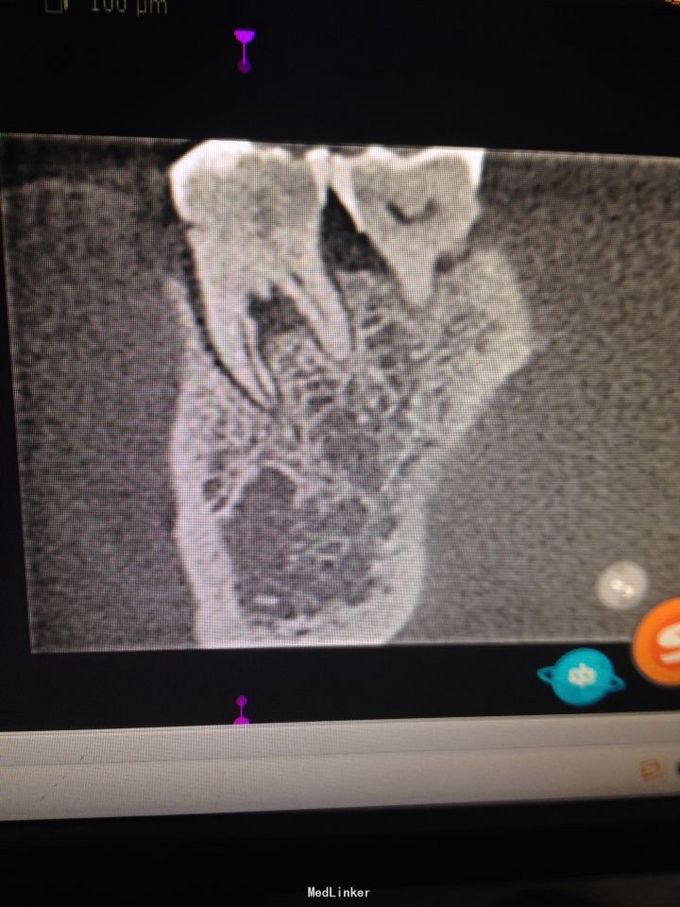

右下六颊侧见窦道,积压见脓液溢出,扪疼明显,扣疼剧烈。牙冠完整,未见龋坏发生。

询问病史有咬硬物硌牙史。诊断:牙根纵折,慢性根尖周炎急性发作。 局麻下微创拔除。

请教是否可以采用分牙方法,保留未折裂牙根,与后临牙联冠或复合桥方法修复?后期效果如何?